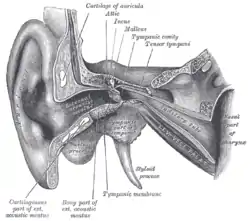

Head and neck of a human embryo eighteen weeks old, with Meckel's cartilage and hyoid bone exposed. External and middle ear, opened from the front. Right side.

External and middle ear, opened from the front. Right side. Chain of ossicles and their ligaments, seen from the front in a vertical, transverse section of the tympanum.